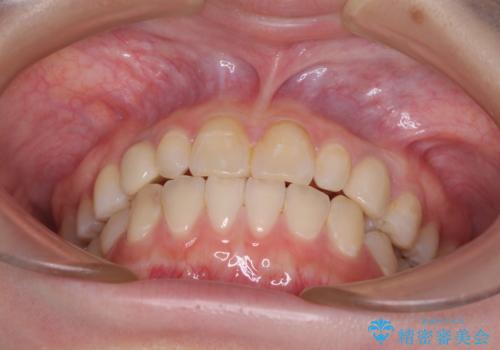

欠損と残存乳歯 矯正治療とインプラント治療

気になっていた部分がすべて解消され、患者様には大変満足していただきました。